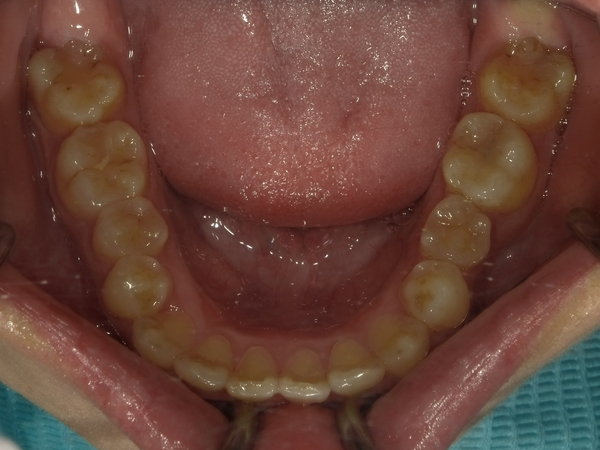

◯ご相談内容:歯並びが気になる◯矯正の種類:マウスピース型矯正「インビザラインGO」◯治療期間:20週間◯治療費用:44万円(税込)